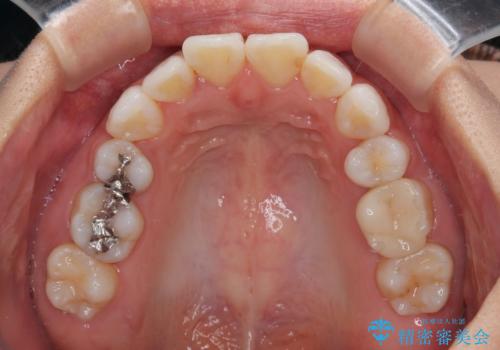

- 上下前歯の後戻りを気にして来院された患者様です。

インビザラインでの治療を希望されていて、デコボコの程度が中等度であり、安価なパッケージにて対応可能と判断されたため、インビザライン・モデレートを用いて矯正治療を行うこととしました。

インビザライン・モデレートは、製作できるアライナーの枚数に制限があるため、移動可能な量に限りがあるものの、インビザライン・ライトよりも枚数が多いため、幅広い症例に対応可能です。